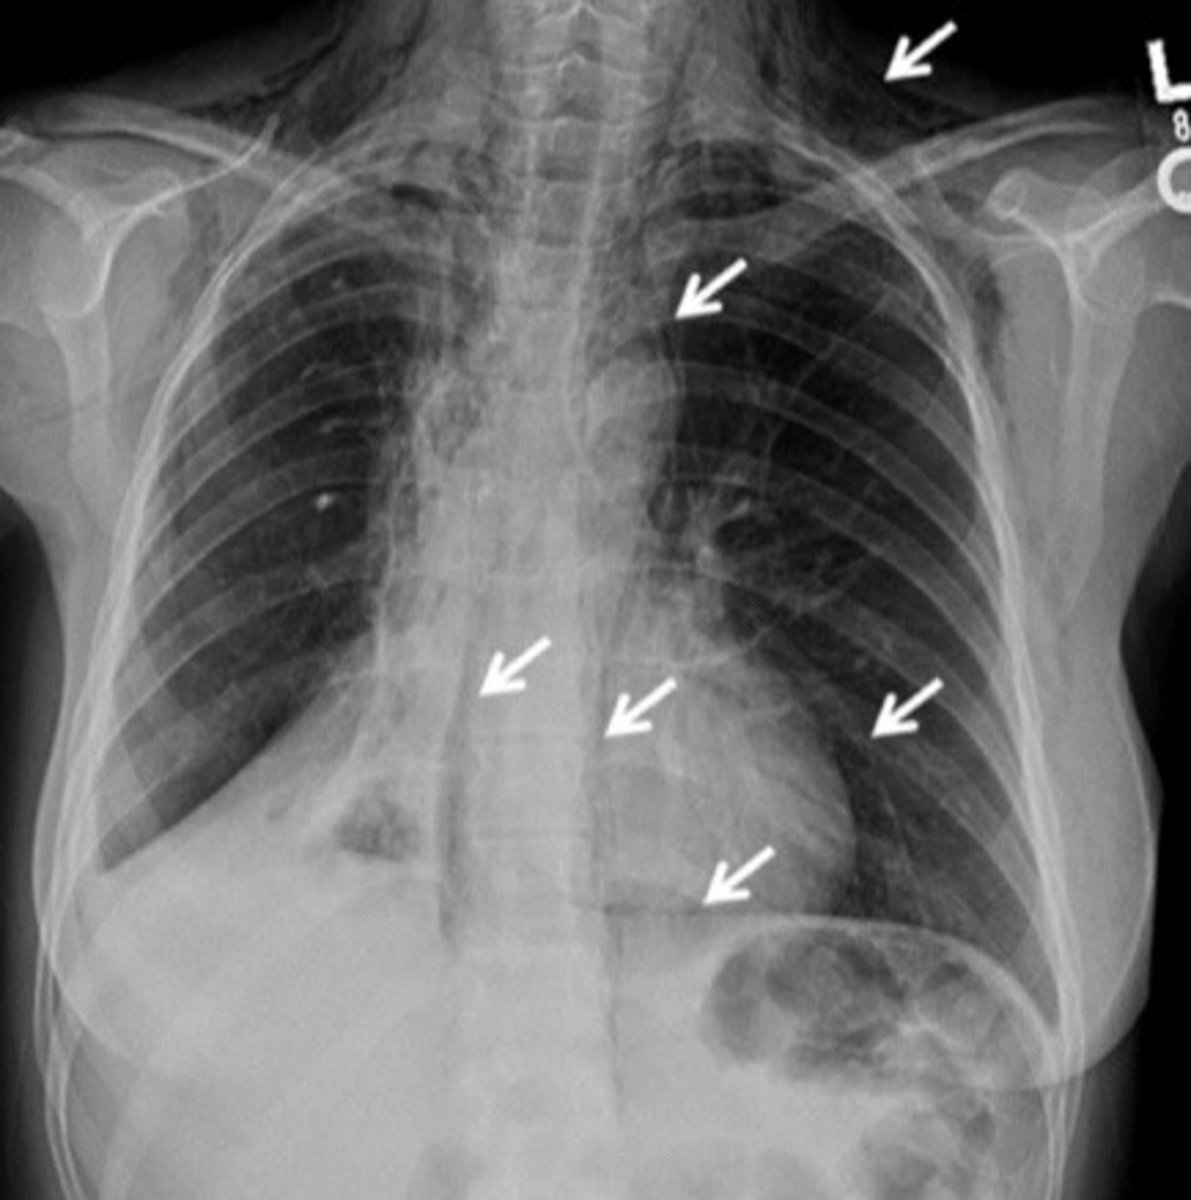

Types of pneumothorax

Iatrogenic: secondary to procedure

Primary spontaneous: healthy pts, no trauma

Secondary spontaneous: known lung dx

92

New cards

GS diagnostic testing for pneumothorax

Upright PA CXR

93

Management of small vs large pneumothorax's

Small: monitor

Large: catheter aspiration

94

How should you manage a tension pneumothorax

Immediate needle decompression

2nd intercostal space, mid clavicular line

95

Mediastinal shift and tracheal deviation on CXR is indicative of

Tension pneumothorax

<p>Tension pneumothorax</p>

96

Visualization of visceral pleural line on CXR is indicative of

Pneumothorax

<p>Pneumothorax</p>